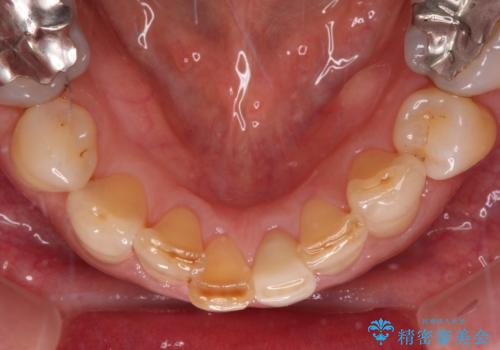

- 下顎前歯が痛んで近医を受診したところ、下顎前歯2本を抜歯してインプラント治療が必要と診断されたとのことで来院された患者様です。

診査の結果、下顎左側中切歯の神経が失活していることが痛みの原因であり、根管治療を行う必要があると診断されました。

根管治療を行った後にオールセラミッククラウンにて補綴することとしました。

隣在歯にも根尖部の炎症が及んでいるように見えましたが、術前診査では神経が失活している様子がなかったため、まずは原因歯から処置を行うこととしました。

初回の根管治療後には痛みが速やかに改善し、6か月後のレントゲン写真では根尖の病変が消失していることが確認できました。